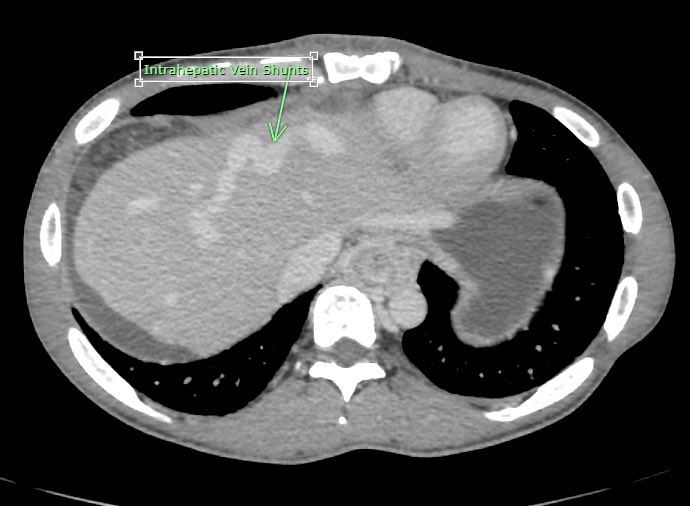

Successful Direct intrahepatic portocaval shunt using gun sight technic! Altered hepatic venous anatomy precluded standard TIPS

David Léon MD tweet mediaDavid Léon MD tweet mediaDavid Léon MD tweet mediaDavid Léon MD tweet media